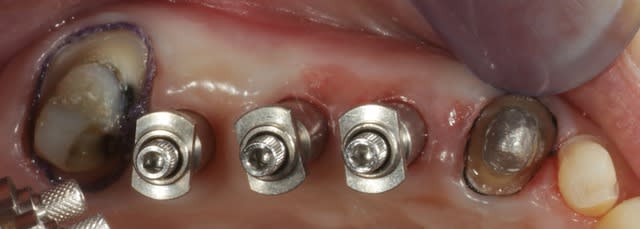

J'ai posé les implants il y a quelques semaines, tout le volume a été conservé, la densité osseuse était pas extraordinaire mais suffisante.

le jour de la prise des empreintes, on peut apprécier le volume osseux maintenu, la gencive est pas extra à cause du bridge provisoire.